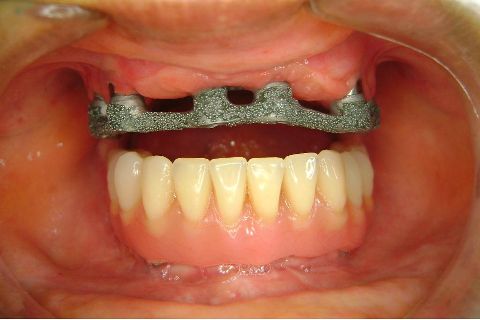

Atualização do caso clínico que já postei, "REABILITAÇÃO EM MAXILA ATRÓFICA COM IMPLANTES", um caso que inclui expansão do rebordo estreito com cinzel e martelo, expansores rosqueáveis, enxerto e instalação dos implantes distais inclinados tangenciando seio maxilar. Inclui esvaziamento do forame nasopalatino e preenchimento com biomaterial para instalação de dois implantes próximos dele. Cirurgia realizada em única sessão, com instalação dos 6 implantes. Para os colegas que não conheceram e/ou esqueceram da apresentação, este é o resumo do caso na fase cirúrgica.http://www.youtube.com/watch?v=BtvexFexRPA&hd=1

FASE PROTÉTICA DA REABILITAÇÃO EM MAXILA ATRÓFICA...incluindo a reabertura, instalação dos minipilares e PTR provisória reembasada sobre os cilindros de proteção.